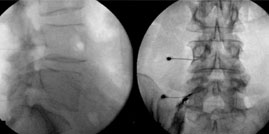

Las fracturas vertebrales que no comprometen la estabilidad de la columna ni que comprimen el canal medular son suceptibles de ser tratadas por el metodo de vertebroplastia que consiste en la inyeccion de cemento oseo (metilmetacrilato) por via percutanea con una incision de unos pocos milimetros (3 mm) en la piel, se dirije una aguja hasta el cuerpo vertebral y con la ayuda de un sistema de rayos X se introduce gradualmente en la vertebra fracturada cemento oseo que va a darle firmeza al cuerpo vertebral fracturado...